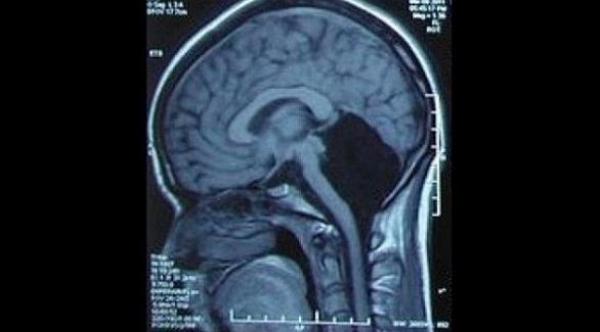

دفعت أعراض الارهاق والدوخة والغثيان شابة من ولا ية شانونغ الصينية(24 عاماً)، إلى زيارة الطبيب المختص، لعمل الأشعة والفحوصات اللازمة ومعرفة أسباب ذلك، والتي كشفت عن وجود نقص في أحد أجزاء الدماغ جعلتها غير قادة على تعلم النطق والكلام حتى الخامسة من عمرها، بالإضافة لعجزها عن المشي حتى السابعة من العمر، بحسب ما ذكر موقع دايلي ميل البريطاني.

وأكد الاطباء أن ذلك النقص في نصف وظائف الدماغ، نجم عنه عجز الشابة عن الأنشطة الحركية كالمشي واللعب والقفز وغيرها، ولاحظ الأطباء وجود سائل نخاعي خاص في الجزء المفقود من الدماغ، وهو ما ساعدها في بقاء الفتاة على قيد الحياة حتى اللحظة الراهنة وممارسة حياتها دون خطر يُذكر، إذ أنها تعتبر الحالة المرضية التاسعة على مستوى العالم التي تعاني من هذا المرض النادر.